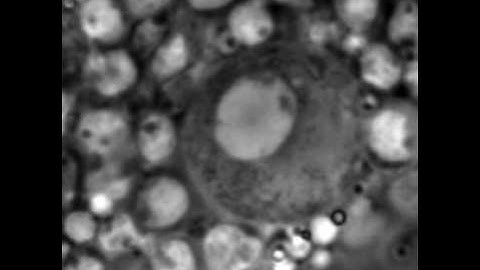

IRB Barcelona: Aged stem cells reprogram their daily rhythmic functions (Cell)